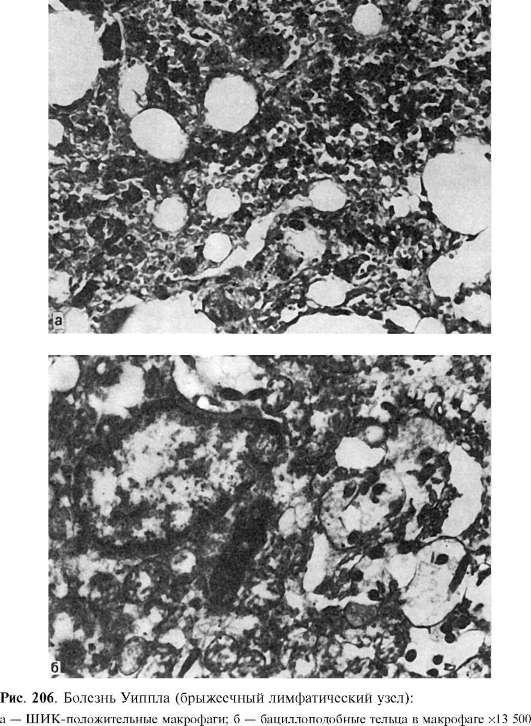

Болезнь Уиппла

Болезнь Уиппла (кишечная липодистрофия) - редкое хроническое заболевание тонкой кишки, для которого характерны синдром нарушенного всасывания, гипопротеин- и гиполипидемия, прогрессирующая слабость и похудание.

Этиология. Многие исследователи в связи с обнаружением в макрофагах слизистой оболочки бацилловидных телец придают значение инфекционному фактору. В пользу инфекционной природы болезни говорит и то, что эти тельца при лечении антибиотиками исчезают из слизистой оболочки и вновь появляются при обострении заболевания.

Патологическая анатомия. Как правило, отмечают уплотнение стенки тонкой кишки и ее брыжейки, а также увеличение брыжеечных лимфатических узлов, что связано с отложением в них липидов и жирных кислот и резким лимфостазом. Характерные изменения обнаруживаются при микроскопическом исследовании. Они проявляются выраженной инфильтрацией собственной пластинки слизистой оболочки кишки макрофагами, цитоплазма которых окрашивается реактивом Шиффа (ШИК-положительные макрофаги). Помимо слизистой оболочки, такого же вида макрофаги появляются в брыжеечных лимфатических узлах (рис. 206), печени, синовиальной жидкости. В макрофагах и эпителиальных клетках слизистой оболочки при электронно-микроскопическом исследовании находят бациллоподобные тельца (см. рис. 206). В кишке, лимфатических узлах и брыжейке, в участках накопления жира обнаруживают липогранулемы.